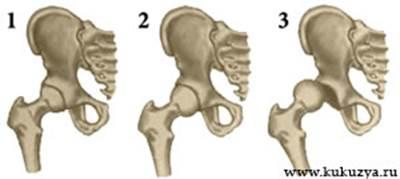

Существует 3 степени дисплазии тазобедренного сустава (врожденного вывиха бедра):

| 1 - Предвывих

2 - Подвывих

3 - Вывих

Предвывих (неустойчивость бедра)

- дисплазия I степени — недоразвитие тазобедренного сустава без смещения головки бедренной кости относительно вертлужной впадины.

Подвывих (врожденный подвывих бедра в тазобедренном суставе)

— дисплазия II степени — недоразвитие тазобедренного сустава с частичным смещением головки бедренной кости относительно вертлужной впадины.

Вывих (врожденный вывих бедра)

— дисплазия III степени — недоразвитие тазобедренного сустава с полным смещением головки бедренной кости относительно суставной впадины.